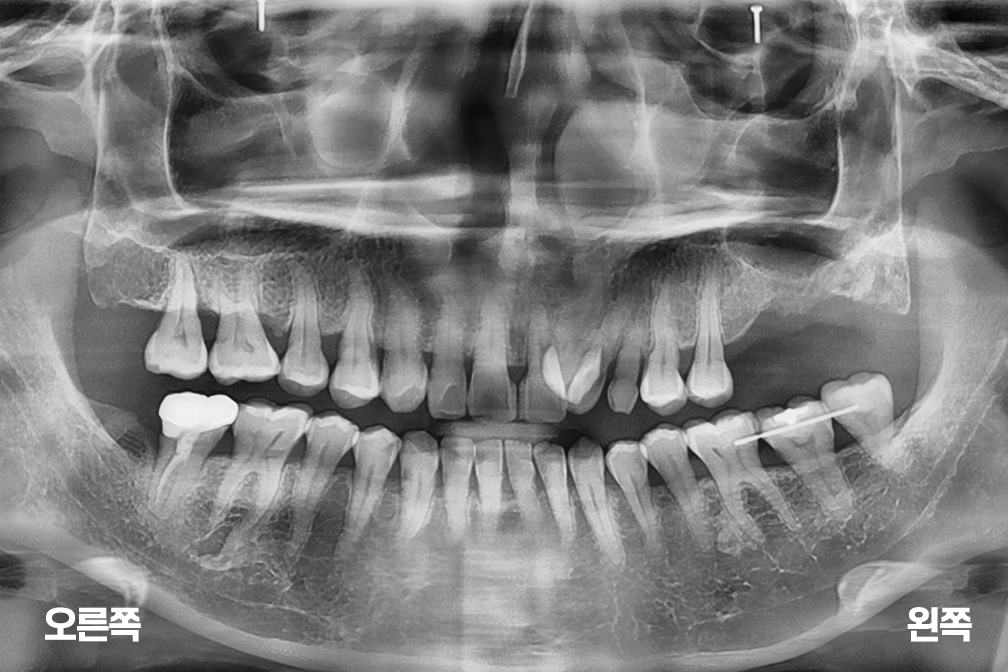

임플란트 상악동 거상술 및 왼쪽 윗 어금니 두개 임플란트 수술

상악동거상술 + 임플란트 수술